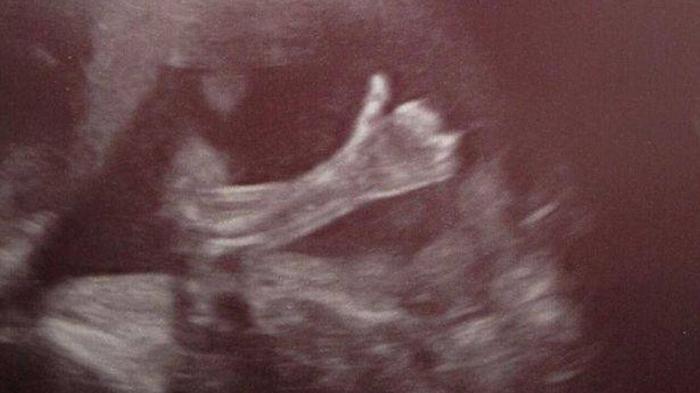

TRIBUNNEWS.COM.COM, MANCHESTER – Foto hasil USG (ultrasonografi) seorang calon ibu di Manchester, Inggris, ini bikin heboh. Betapa tidak, foto itu menunjukkan sang jabang bayi mengacungkan jempolnya.

Acungan jari jempol si jabang bayi itu seolah-olang hendak menyampaikan pesan ke orangtuanya kalau kondisinya baik-baik saja. Kejadian ini membuat sang orangtua, Cheryl Stevenson dan Paul Schofield meras takjub.

”Foto itu diambil saat usia kehamilan saya memasuki 20 minggu. Saya terkejut saat melihat foto USG itu,” katanya seperti dikutip dari Metro, Selasa (17/2/2014).

Paul menimpali si jabang bayi sempat menggerakkan tangannya berulang kali sesaat sebelum mengacungkan jempol.